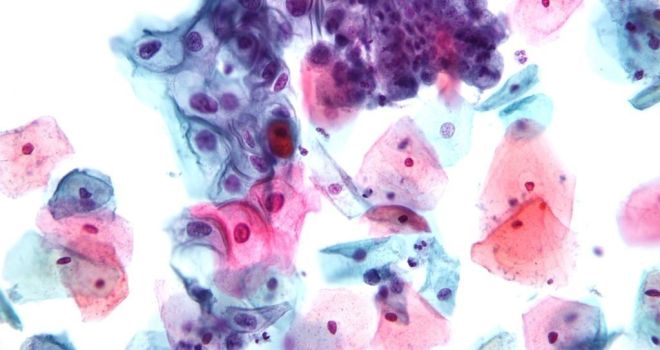

При выявлении хламидиоза обязательно в лечебных целях назначают антибактериальные препараты. Но бороться с возбудителями данной инфекции сложно, так как весь жизненный цикл хламидий проходит в клетках организма. Бактерии получают энергию и размножаются внутри клеточных структур. Из-за этого от них сложно избавиться, ведь оболочки клеток надежно защищают бактерии от влияния противомикробных средств.

Поэтому для лечения хламидиоза необходимо выбирать такие препараты, которые могут проходить сквозь клеточные оболочки и накапливаются в пораженных тканях. Используют преимущественно антибиотики с широким спектром действия. Исследования показали, что они чувствительны к тетрациклиновым препаратам, макролидам, фторхинолонам.

Но данные, полученные в результате анализов, не всегда коррелируют с данными об эффективности их применения на практике. При исследованиях in vitro (вне живого организма) выявляется, что хламидии чувствительны к пенициллинам. На практике их не используют из-за того, что необходимы чрезмерно высокие дозы для получения результата.